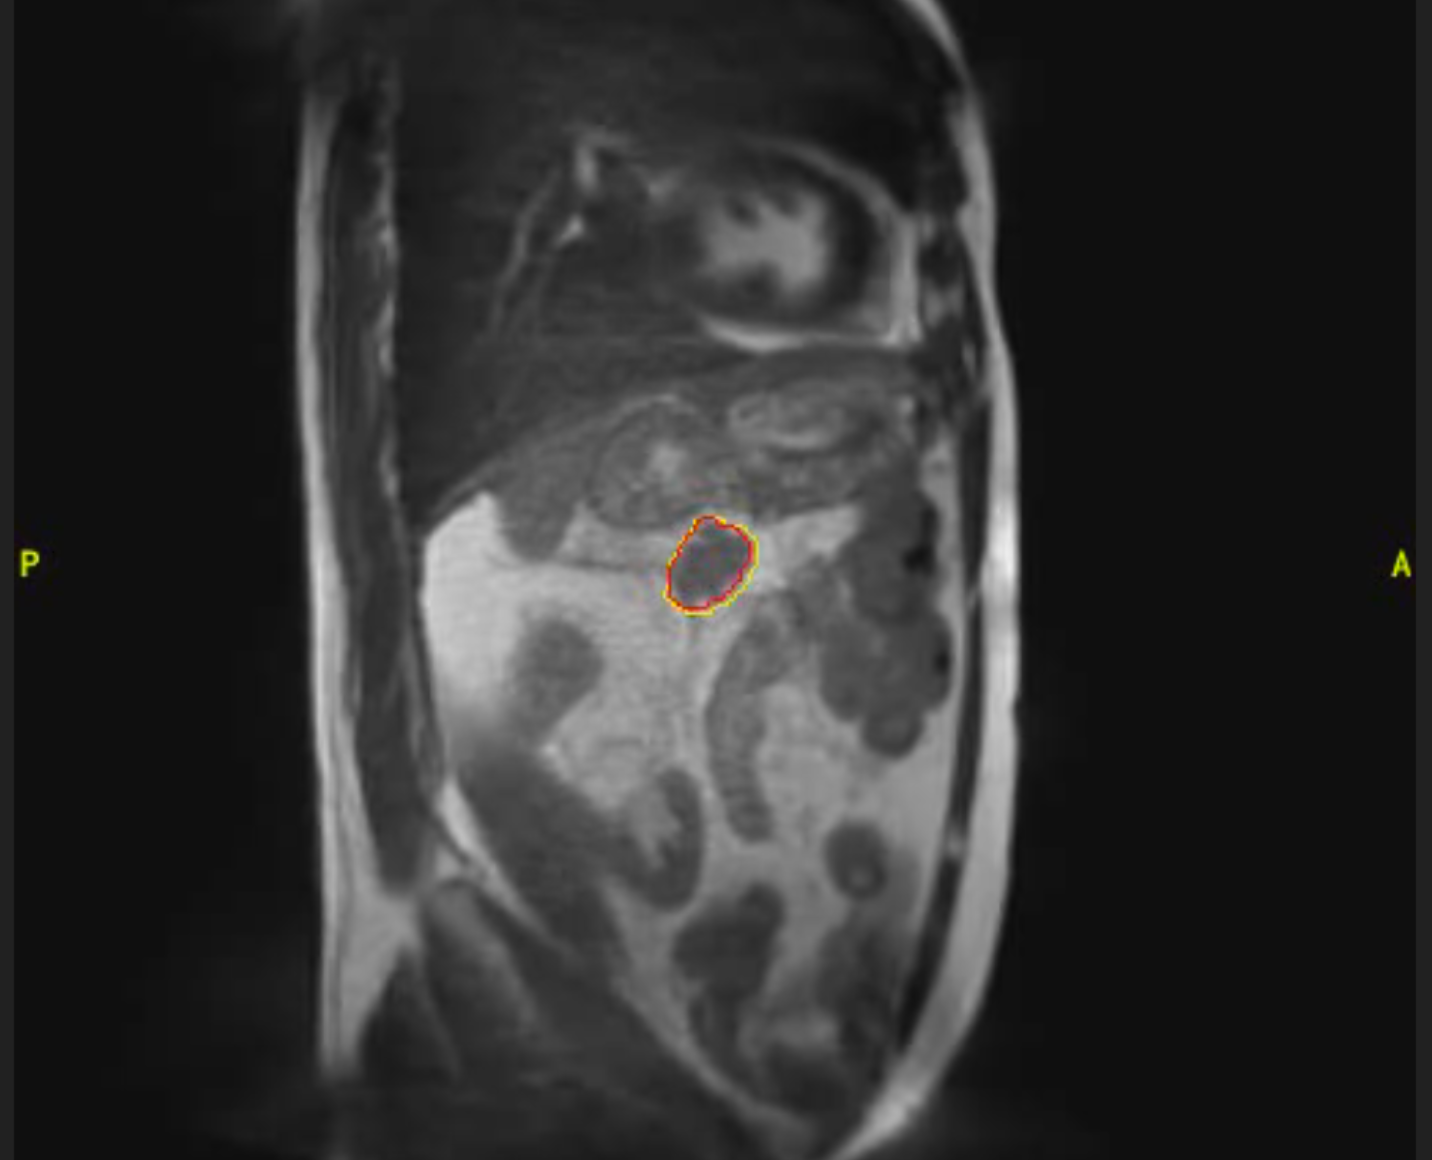

Cáncer de páncreas

Mujer de 46 años con diagnóstico de adenocarcinoma de cabeza de páncreas localizado. Recibe tratamiento con quimioterapia durante 5 ciclos y seguidamente radioterapia con intención radical en Acelerador Lineal con Resonancia (MRIdian): 5 fracciones en 5 días. Presentó buena tolerancia al tratamiento, sin efectos adversos destacables y tras 3 meses de finalizado el mismo se encuentra con enfermedad estable.

Imagen 2